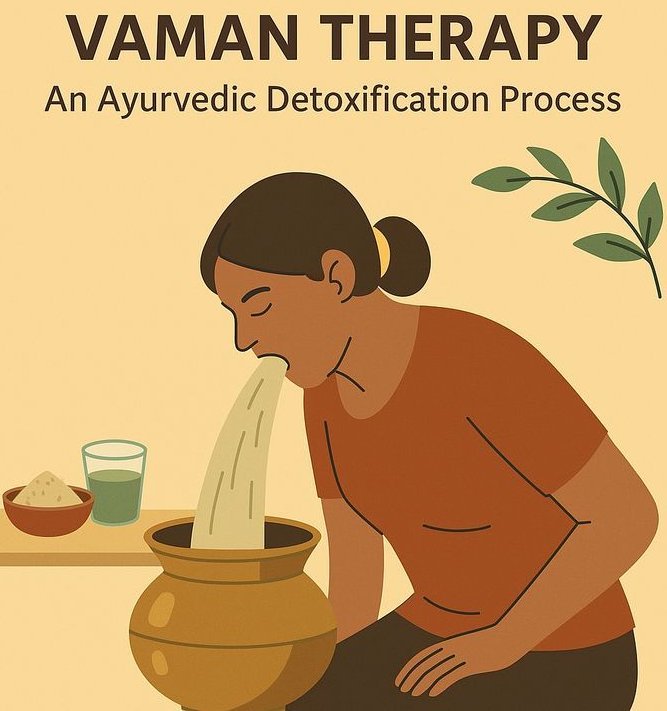

Panchakarma

Panchakarma is a deep Ayurvedic detoxification and rejuvenation therapy that cleanses the body of toxins, balances the doshas, and restores overall health through five cleansing procedures.

Digestive problems for ayurvedic treatment

Get natural, holistic relief from digestive problems with Ayurvedic treatment that balances your doshas and strengthens your digestive fire (Agni).